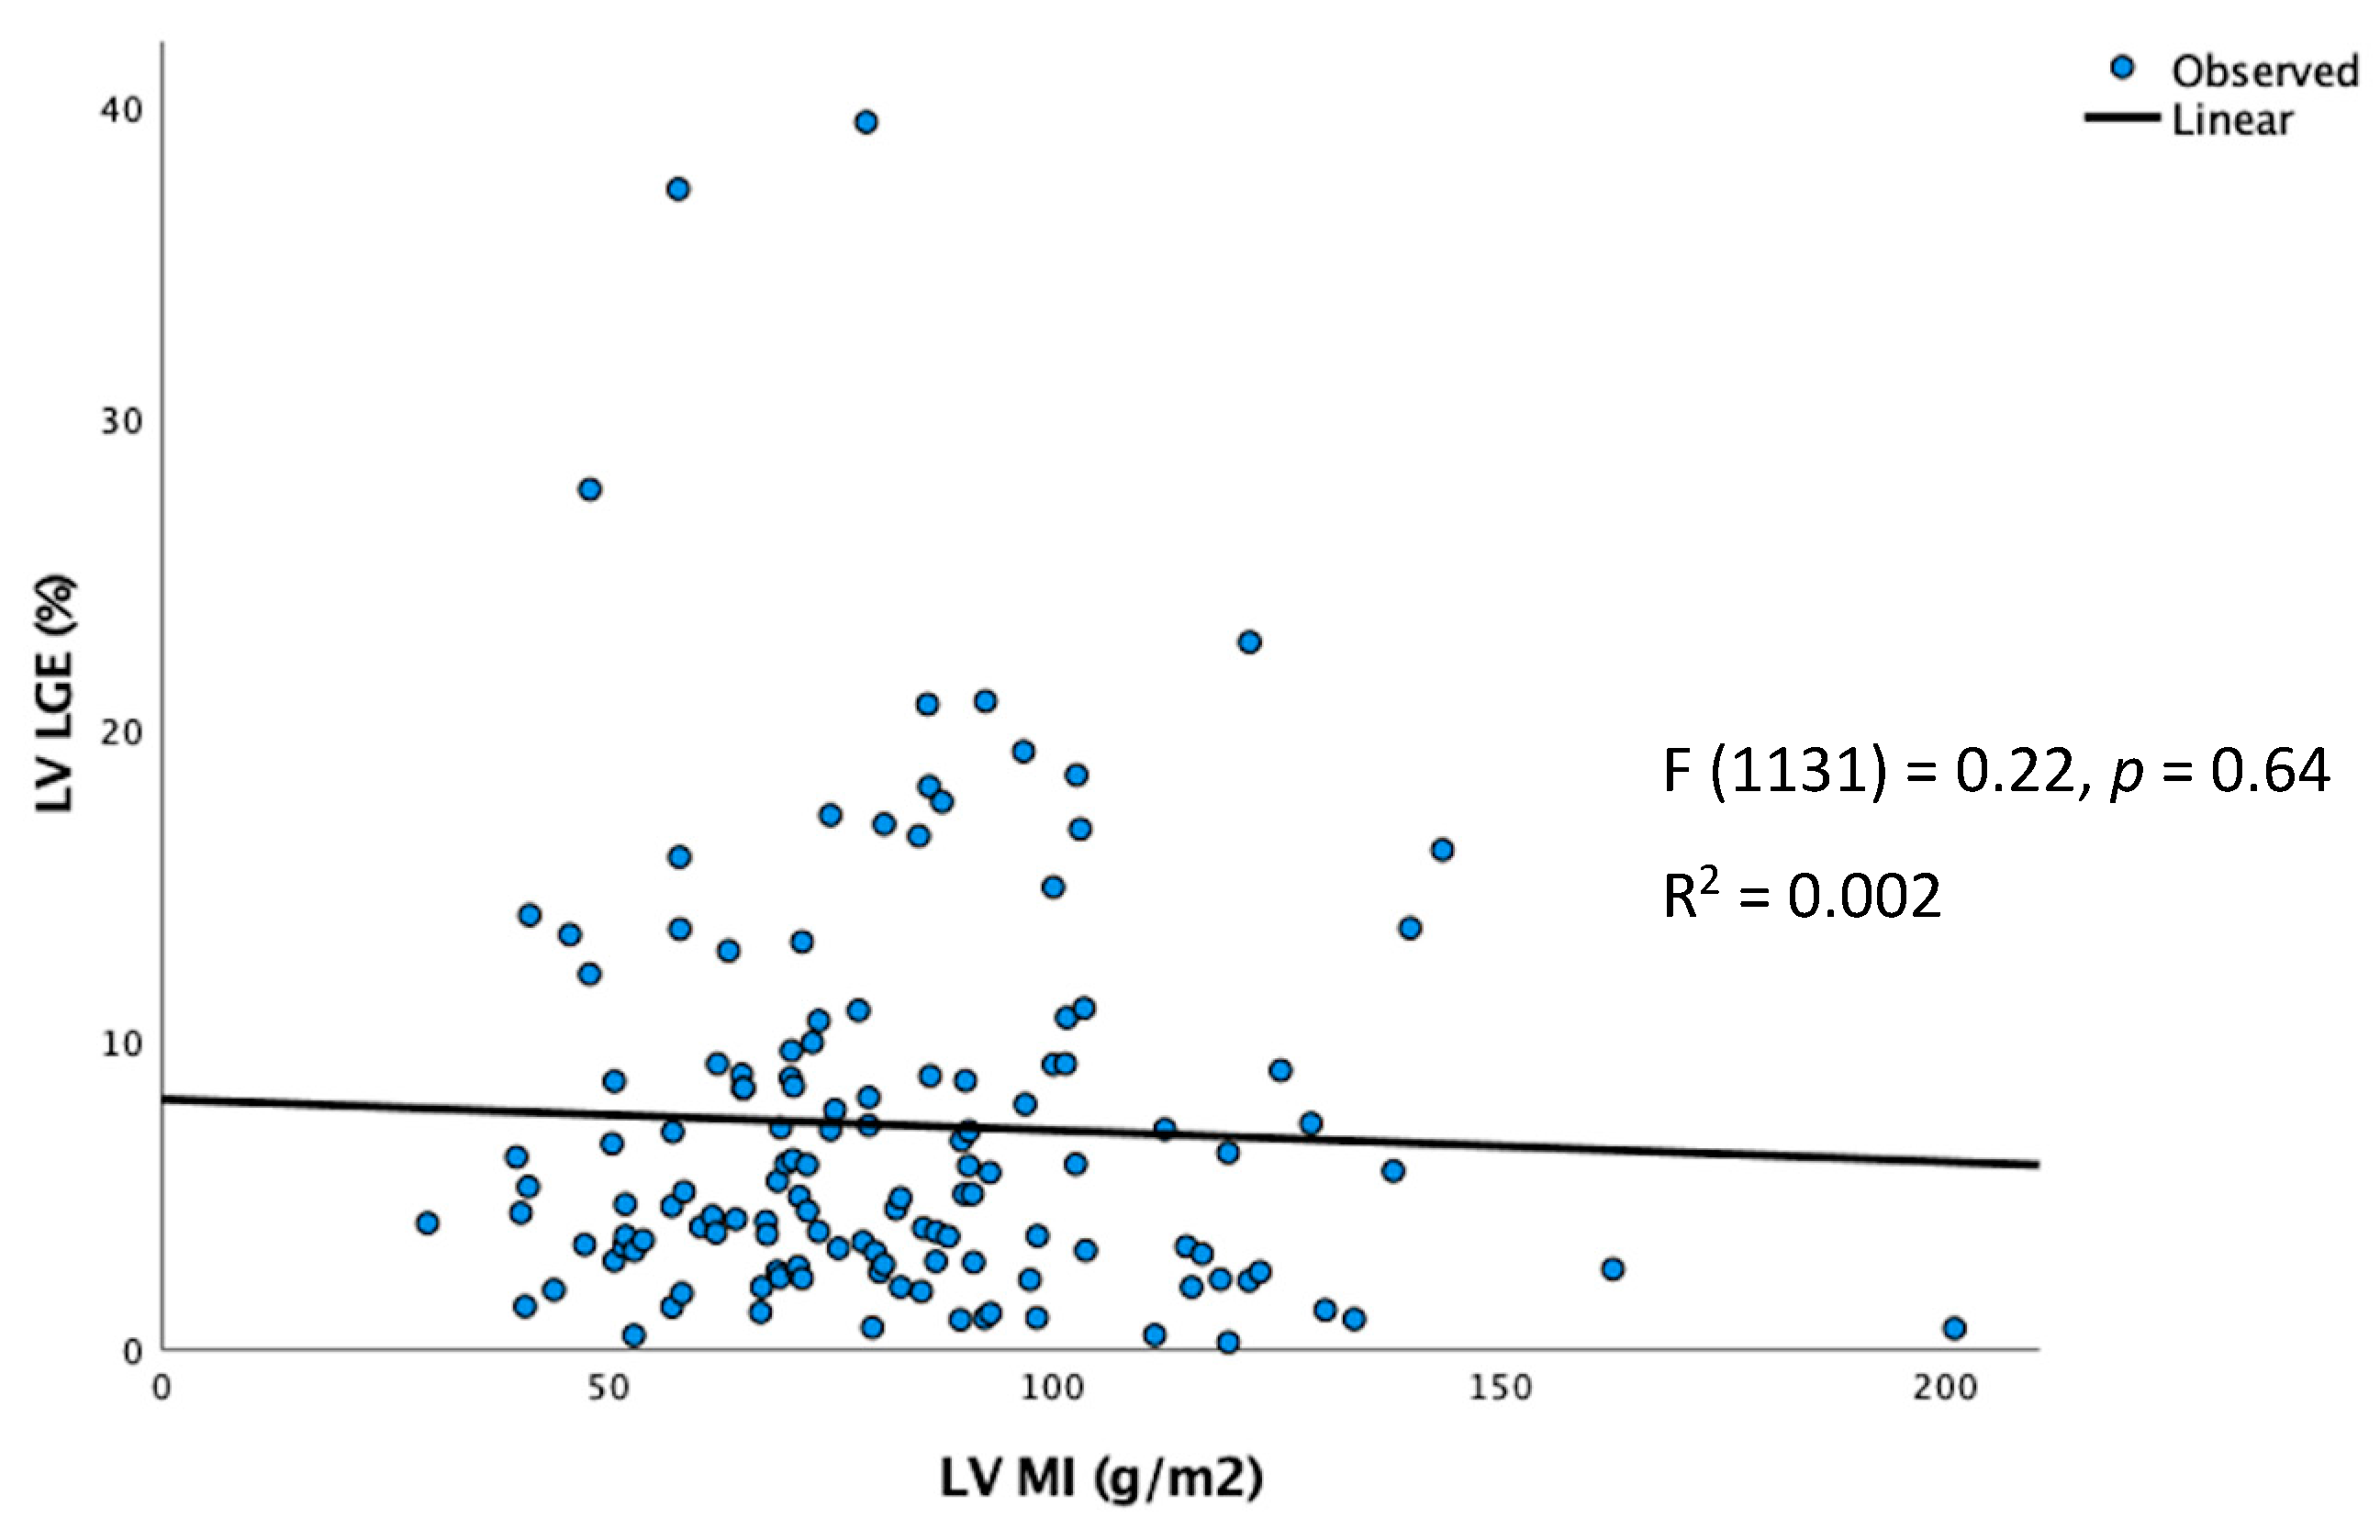

6.1. Correlation of LVWT and LVMI with LV Fibrosis

- LVMI > 85 g/m2 and LVLGE > 6% are associated with VA.

- LVWT using TTE or CMR was only weakly correlated with LVMI on CMR.